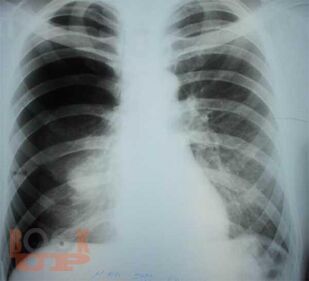

Спонтанный пневмоторакс

Ханнанов Н. И. Спонтанный пневмоторакс : учебное пособие для врачей / Н. И. Ханнанов, В. В. Фаттахов, М. Н. Насруллаев. - Казань : КГМА, 2020. - 40 c. - Текст : электронный // ЭБС "Букап" : [сайт]. - URL : https://www.books-up.ru/ru/book/spontannyj-pnevmotoraks-16035604/ (дата обращения: 11.11.2025). - Режим доступа : по подписке.